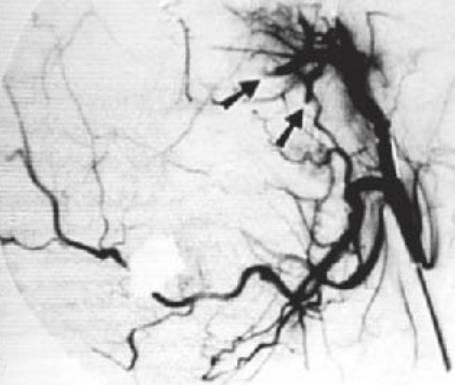

- Lesiones de mucho flujo: arteriales con fístulas arteriovenosas (fig. 8.11), que se presentan con dientes móviles y, en ocasiones, dolorosos así como pulsos palpables y auscultables, encías sangrantes y afectación ósea.

- Se precisa la realización de una angiografía de sustracción digital (fig. 8.11B) para establecer el diagnóstico definitivo de los vasos nutricios y la distribución de la lesión.

- Como ayuda al diagnóstico, puede realizarse una angiografía de resonancia magnética, pero la angiografía de sustracción digital presenta como ventaja que permite la embolización al mismo tiempo.

- Las lesiones de flujo alto requieren la embolización selectiva de los vasos, pero recidivarán después de la embolización debido a la revascularización a partir de la irrigación contralateral y a la recanalización de la arteria embolizada. Suele requerirse la práctica de embolizaciones y resecciones repetidas de toda la lesión, lo que incluye la reconstrucción de la mandíbula.